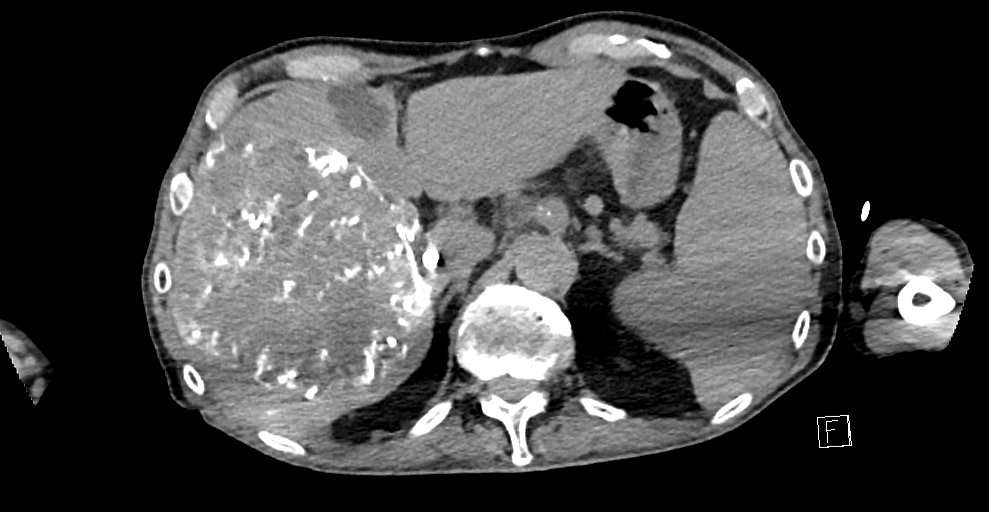

Case 1

79 M with PMH of CKD, HLD, prostate cancer s/p prostatectomy + radiation presenting with feelings of fogginess, upset stomach, and diarrhea. Originally worked up at OSH, imaging concerning for a hepatic mass.

148/77 mmHg / 95 bpm / 15 breaths/min / 98.1°F / 98 ORA

sclera anicteric, no jaundice

AST 112, ALT 34, Alk Phos 202, CEA 2, CA 19-9 4